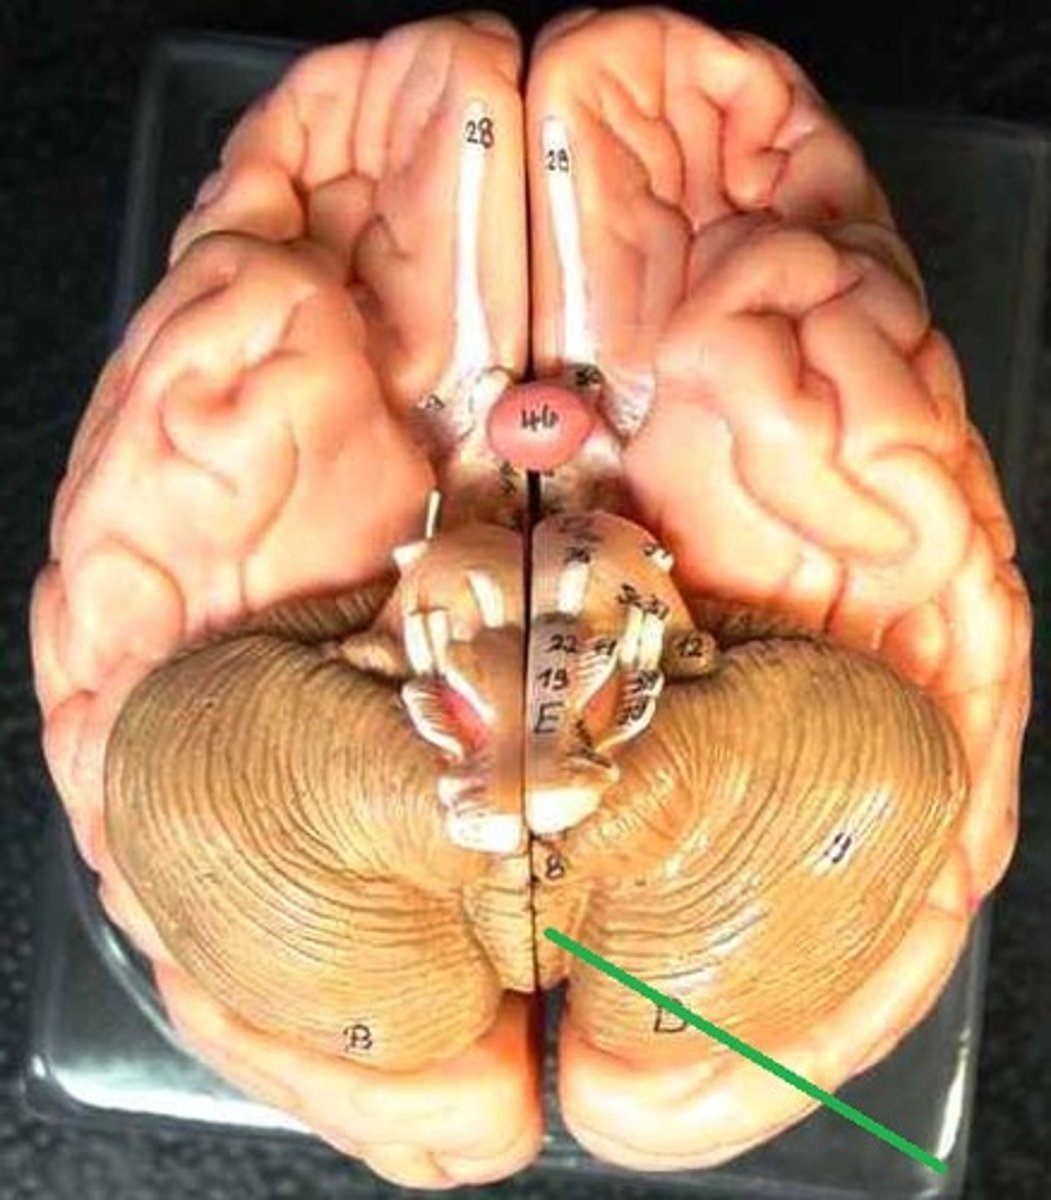

anterior lobe of cerebellum upper half

Lobe of cerebellum that is separated from anterior via primary fissure (bottom half)

posterior lobe of cerebellum

vermis of cerebellum

The tissue between the two cerebellar hemispheres: concerned with regulation of muscle tone for posture and locomotion.

Nodule of cerebellum

has important connections to the vestibular nuclei and uses information about head movement to influence eye movement

flocculonodular lobe of cerebellum

part of the vestibulo-ocular reflex system and is used to help stabilize gaze during head rotation about any axis of space.

tonsil of cerebellum - planning of motor activity

cerebellar peduncles

4th ventricle